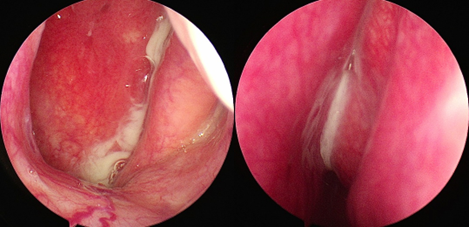

鼻内镜检查单侧中鼻道脓性物(下图)

鼻内镜检查中鼻道可见脓性鼻涕、水肿或息肉